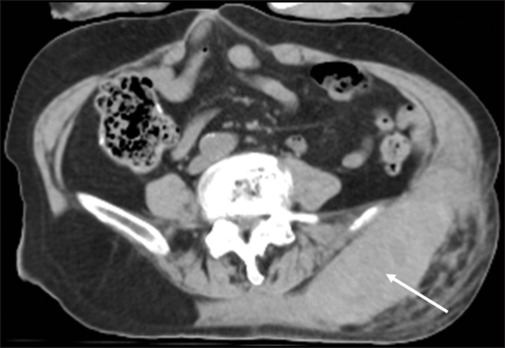

Blunt Trauma without Elevated Fibrin Degradation Product.

{"title":"Blunt Trauma without Elevated Fibrin Degradation Product.","authors":"Youichi Yanagawa, Michika Hamada, Chihiro Maekawa, Noriko Tanaka, Kenji Kawai, Soichiro Ota","doi":"10.4103/jets.jets_107_24","DOIUrl":null,"url":null,"abstract":"","PeriodicalId":15692,"journal":{"name":"Journal of Emergencies, Trauma, and Shock","volume":"17 4","pages":"255-256"},"PeriodicalIF":0.7000,"publicationDate":"2024-10-01","publicationTypes":"Journal Article","fieldsOfStudy":null,"isOpenAccess":false,"openAccessPdf":"https://www.ncbi.nlm.nih.gov/pmc/articles/PMC11792760/pdf/","citationCount":"0","resultStr":null,"platform":"Semanticscholar","paperid":null,"PeriodicalName":"Journal of Emergencies, Trauma, and Shock","FirstCategoryId":"1085","ListUrlMain":"https://doi.org/10.4103/jets.jets_107_24","RegionNum":0,"RegionCategory":null,"ArticlePicture":[],"TitleCN":null,"AbstractTextCN":null,"PMCID":null,"EPubDate":"2024/9/20 0:00:00","PubModel":"Epub","JCR":"Q3","JCRName":"EMERGENCY MEDICINE","Score":null,"Total":0}